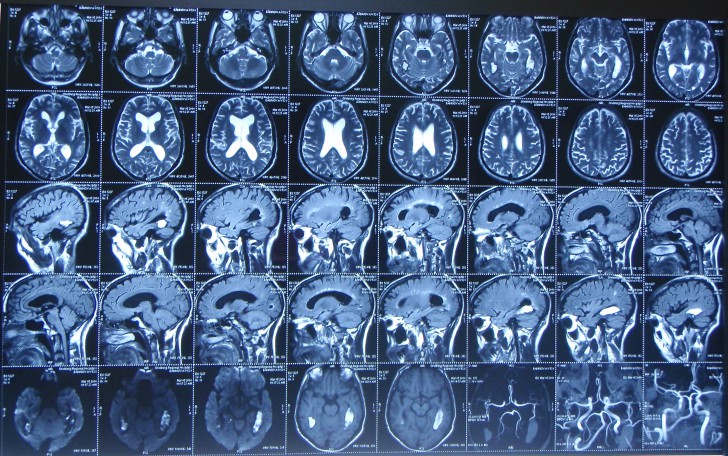

КТ головного мозга детям показывает состояние головного мозга, костей черепа, глазных орбит и пазух. МРТ дает больше информации о сосудах, мягких тканях и нервной системе маленького человека. Показания к проведению процедуры:

Снимки КТ и МРТ обладают высокой точностью и могут показать следующие патологии:

Исследование позволяет оценить все кости черепа ребенка, в том числе височную кость и ее структуры, серое вещество мозга, белое, область полушарий и ствола мозга, ликворопроводящую систему. При компьютерной томографии головы ребенка можно дополнительно оценить область глазницы и носовых придаточных пазух.

Магнитно-резонансная томография у детей выполняется для диагностики широкого спектра заболеваний: патологии головного и спинного мозга, скелета, органов брюшной полости, органов малого таза, мягких тканей.

КТ хорошо показывает твердые ткани, инородные тела, свежие кровоизлияния. Тогда как опухоли или давние органические поражения мозга видны недостаточно, иногда совсем незаметны. Чтобы диагностировать патологические изменения мягких тканей, требуется МРТ.